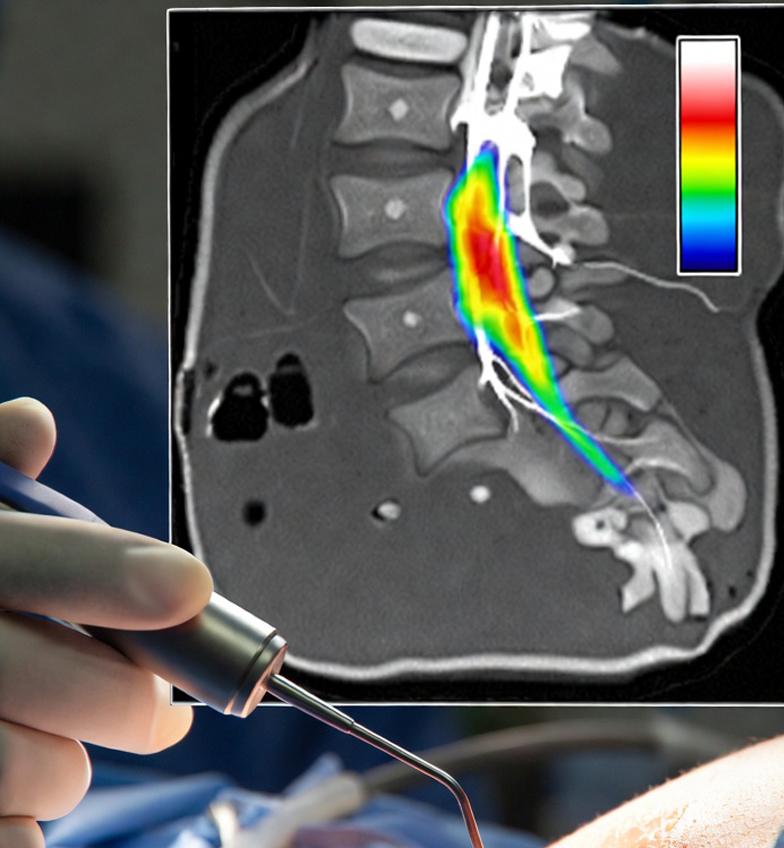

Future surgical platforms willevolve to include High Resolution Nerve Localization (HRNL) systems that arecapable of performing a complex volumetric multi-dimensionalanalysis that provides accurate, quantitative measurements that reveal theprecise location of nerves in the surgical field.